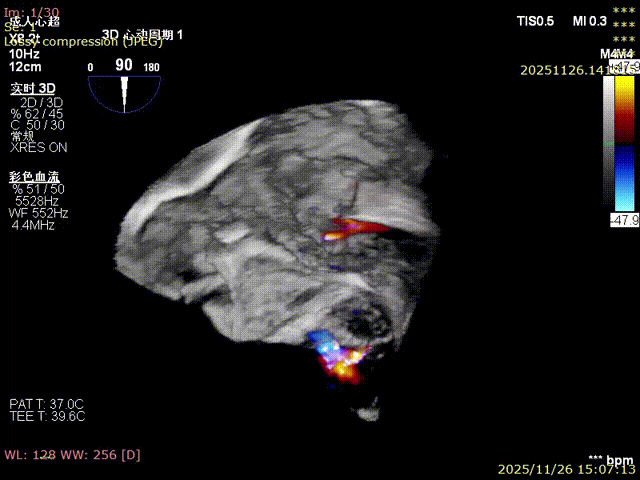

3D image